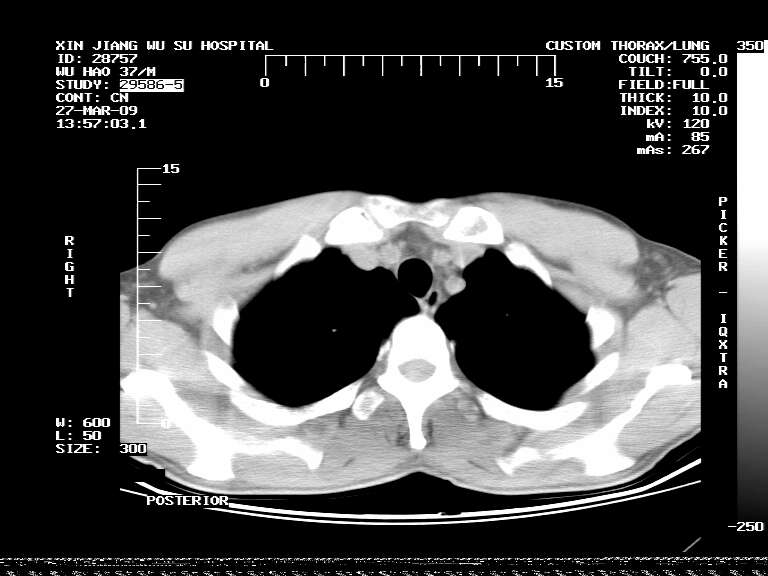

男,37岁,体检胸透发现阴影。

患者体检发现 无症状 左肺下叶占位,边缘模糊,可见血管聚束、分叶、胸膜牵拉,增强呈不均匀性强化。 首先考虑左肺下叶周围型肺癌,建议穿刺活检。

左肺下叶见一结节病变,边缘欠清不光滑,与胸膜粘连且胸膜局限性增厚,注药后呈环形强化,动脉期壁呈明显点环状强化,静脉期壁强化减低,中心密度低无强化,灶周无明显的卫星灶和水肿区(晕征)---考虑周围性肺癌,不除外感染性病变,建议穿刺活检。

左肺下叶软组织病灶,密度较高,内见点状钙化,其周围见子灶,邻近胸膜扁平样增厚.c+病灶强化明显,中心强化弱.诊断:左肺下叶结核瘤.

左肺下叶大片实变影,内靠胸膜见不规则更高密度结节灶,边缘强化,相邻胸膜增厚,胸膜下脂肪线存在。考虑炎症,结核可能。